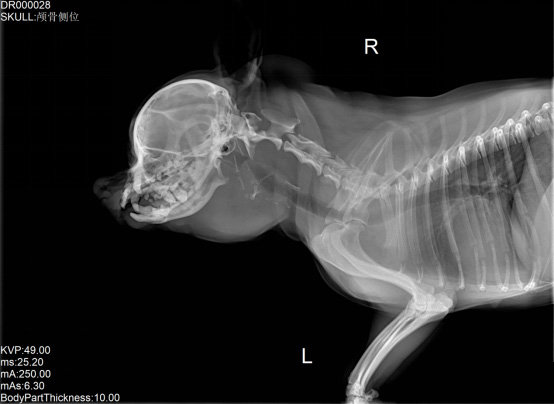

寵物DR是專業(yè)用于寵物X光拍攝的數(shù)字化X射線檢查,輔助寵物醫(yī)生進(jìn)行及時(shí)精確的診療。寵物DR主要包括五大主要部件,數(shù)字X光探測器,高壓發(fā)生器,球管,機(jī)架,寵物專用的DR工作站軟件。寵物DR由于采用數(shù)字技術(shù),自動(dòng)成像處理,模擬X線圖像向數(shù)字化X線圖像的轉(zhuǎn)變。寵物DR與傳統(tǒng)模擬X光機(jī)相比有什么優(yōu)勢(shì)呢?采集時(shí)間10毫秒以下,成像時(shí)間僅為3秒,較高的空間分辨力和低噪聲率,提高了病灶的檢出率,避免漏診誤診等問題。減少X線對(duì)人體照射的不良影響寵物DR照片是您最佳的選擇。提高寵物醫(yī)生工作效率,總而言之,選擇寵物DR是寵物醫(yī)院的最佳選擇。寵物醫(yī)學(xué)影像學(xué)實(shí)現(xiàn)全數(shù)字化和無膠片化升級(jí)發(fā)展提高技術(shù)水平。